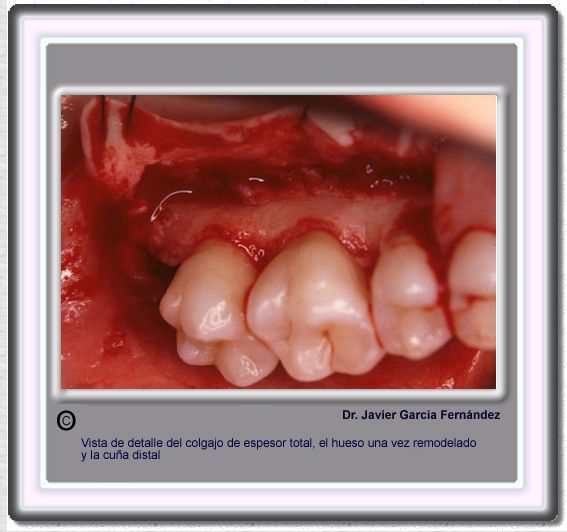

image 170